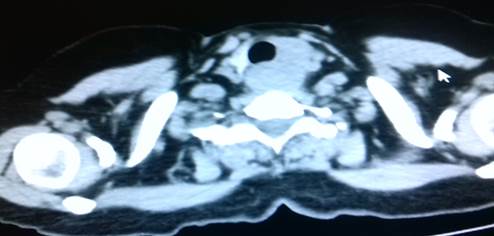

Pruebas de laboratorio: se aprecia leucocitosis en 12.000cel/mm3 y luego progresa a 24.500cel/mm3, polimorfo nuclear 90%, valores de glucosa en sangre elevada. Se le realiza rayos x de cuello (Figura 2. Anexos), y ecosonograma de región cervical, donde se describe una lesión ocupante de espacio alrededor de la tráquea hacia el lado izquierdo, de 4x 2 cm, heterogénea de bordes bien circunscritos. No presenta vascularidad al uso del Doppler. El lóbulo izquierdo del tiroides, muestra efecto de masa en su cara inferior. Concluye con una lesión ocupante de espacio en región traqueal izquierda sugerente de absceso frio. Se le realiza estudio de tomografía computarizada de cuello (Figura. 3, 4, 5. Anexos), y tórax, apreciando en región lateral izquierda del cuello, hiperdensidad paralela a la tráquea y glándula tiroidea, haciendo efecto de masa compresiva sobre las estructuras cercanas.

Figura 5. Tomografía axial computarizada de región cervical. apreciando en región lateral izquierda del cuello, hiperdensidad paralela a la tráquea y glándula tiroidea, haciendo efecto de masa compresiva sobre las estructuras cercanas.

Fuente: Fotografía realizada por Dra. María Pulgar.